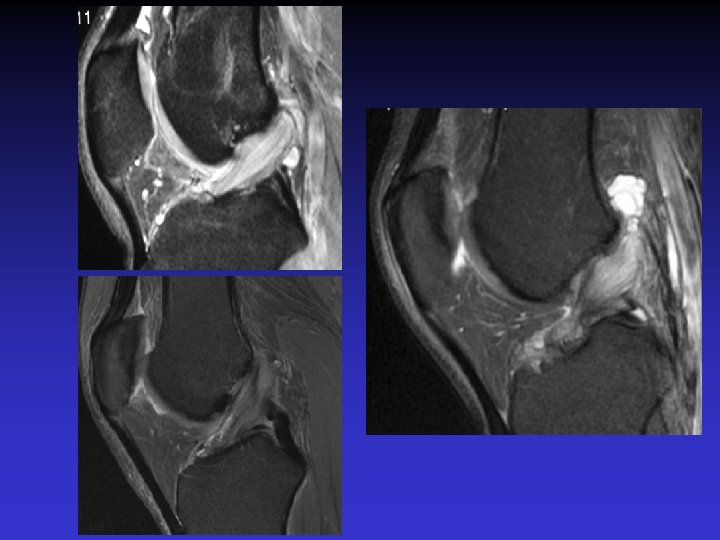

GEODES SYNOVIALES • En regard des zones d’insertion fémorale et / ou tibiale • Hypo TI Hyper T 2 • Rehaussement possible après Gado IV

GADO

ASSOCIATION A DES KYSTES MUCOIDES • Dans près de 50% des cas • Au contact ou à distance du LCA